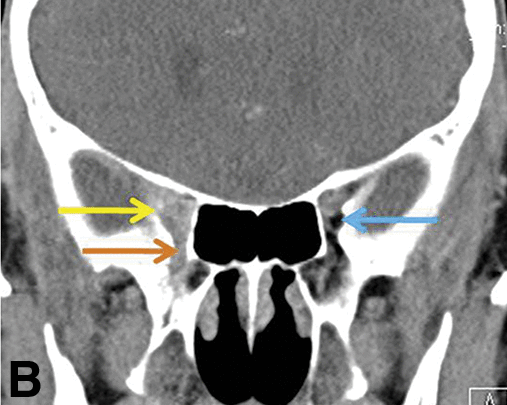

CN V2 branches into the infraorbital nerve, which exits the maxilla at the infraorbital foramen, which has a little bit of very useful fat! Also look for widening of the infraorbital canal.

Right normal foramen vs. left perineural spread from skin cancer on the cheek: